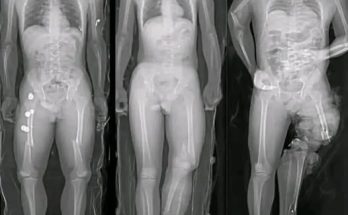

Remembering the Karatu School Bus Tragedy: Eight Years On Eight years have passed since one of Tanzania’s darkest days — the Karatu school bus tragedy. On May 6, 2017, 32 …